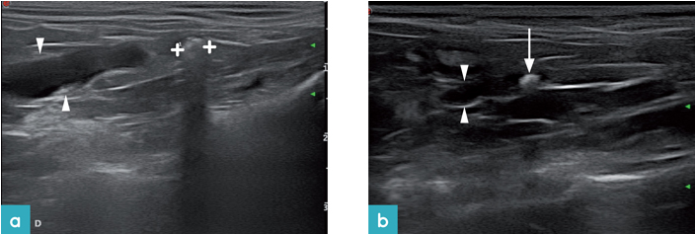

在一些情况下,输尿管壁增厚和肠脂肪周围的回声反应性增加存在相关性(图35)。输尿管梗阻的一种治疗方法是放置皮下输尿管旁路装置或输尿管支架(图36)。